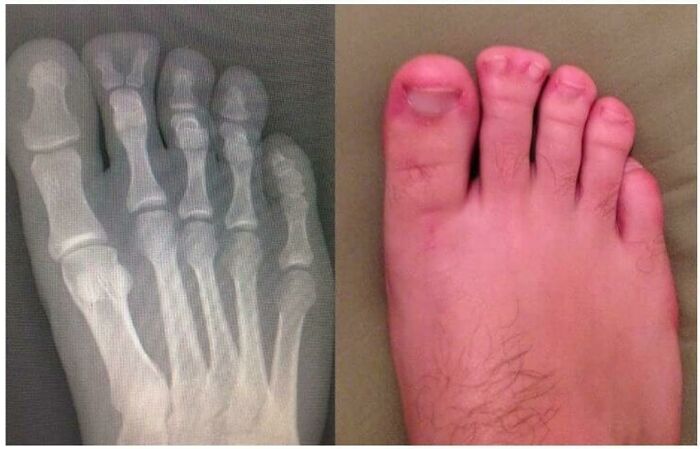

What? How?